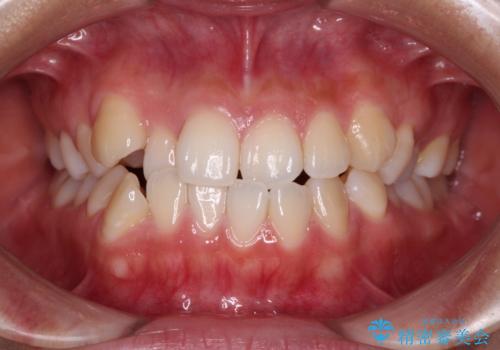

- 前歯のデコボコを治したいとのことで来院された患者様です。

インビザラインによるマウスピース矯正も適用となる歯列でしたが、できる限り楽して、短期間で治したいとのことで、ワイヤー装置にて矯正治療を行うこととしました。